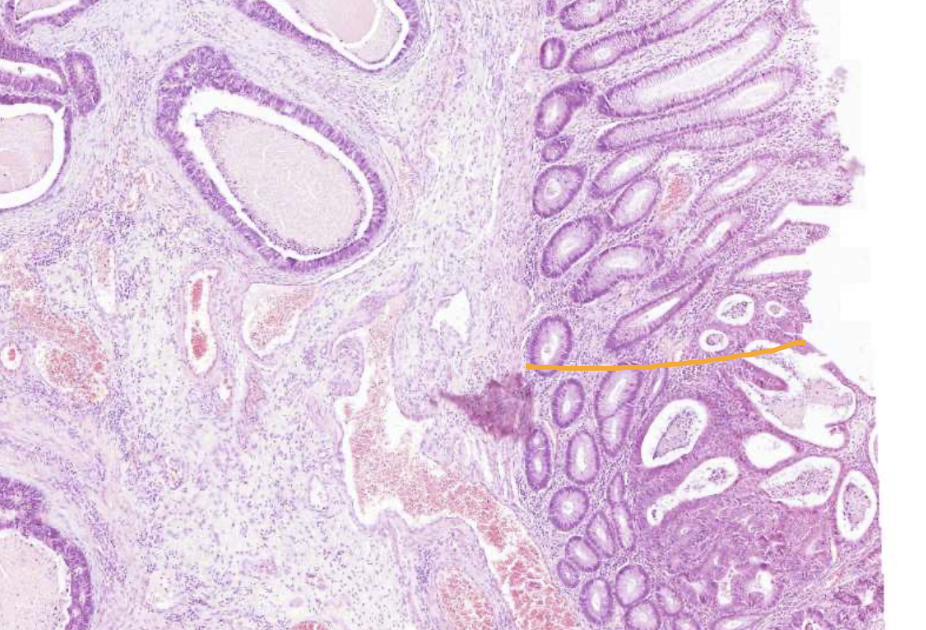

Superficial growing colon adenocarcinoma

On the “right” side of the muscularis mucosa

Invasive colon adenocarcinoma

On the “wrong” side of muscularis mucosa

Well differentiated colon adenocarcinoma - Invasive cancer glandular structures in submucosa

Not a good prognosis

Well differentiated colon adenocarcinoma - Large groups of invasive cancer cells on wrong side of muscularis externa

Large clusters of cancer structures

Forming into glandular structures

Large nuclei

Varied location of nuclei

Tumour has infiltrated all the walls of the intestine, reached the fat tissue and also the muscle tissue here to some extend